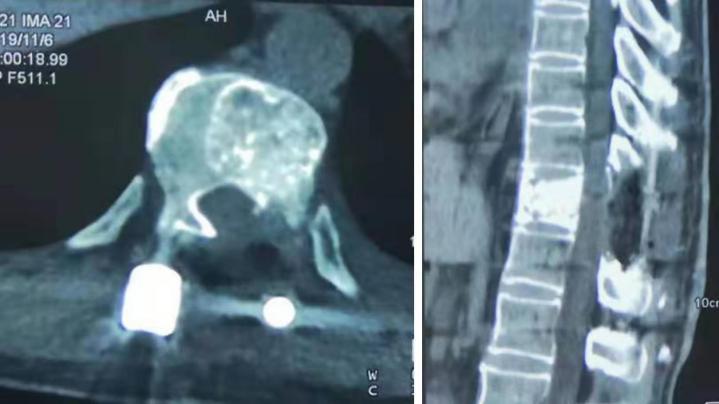

术后复查x线、CT

术后患者背部疼痛消失,双侧足底麻木感逐渐缓解,没有出现任何并发症,术后第二天拔除引流管,在支具保护下行走,术后第七天出院。

患者出院1周回院复查,外固定支具保护下地行走无任何问题,双侧足底麻木感消失,谭院长对患者术后康复从饮食及运动等多个方面进行了亲切的指导,患者及家属对潍坊市中医院东院区脊柱骨科全体医护人员不辞辛苦的努力表示感谢,合影留念。